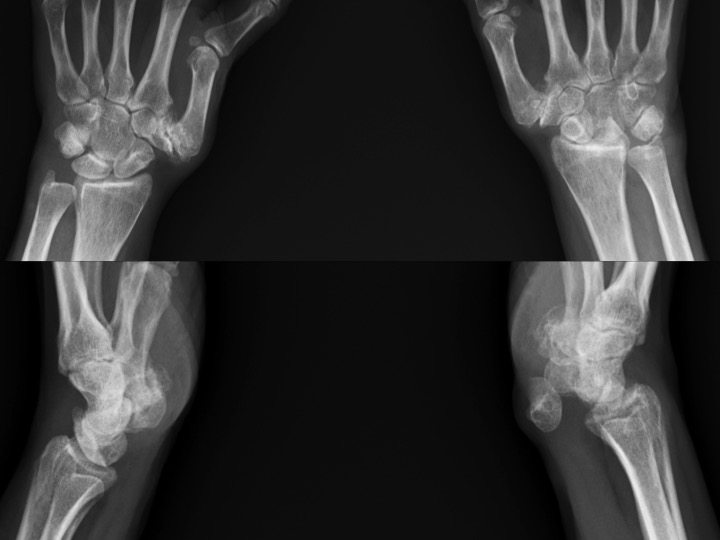

53F 6-8 mos pain with mass in carpal tunnel

What makes this amusing (to me) is that the radiographs (slide 5) were done and reported (by me) 4 days prior to MRI. Patient claims prior work related injury, though this was not the focus of the office visit note. The hand surgeon interpreted the XR in his note as no scapholunate interval widening, no DISI (thats the funny part). MRI was ordered to evaluate mass in the carpal tunnel region. The patient moved a little because she was in alot of pain. The Sag PDFS images show the median nerve being stretched and compressed anterior to the chronically dislocated lunate. (the lunate seems to be happy) Reference article.

Lunate dislocation